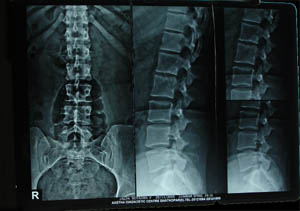

Lumbosacral spine 1

Normal lumbar spine seen in frontal & lateral view. One can see pedicles, spinous process, facet joints, transverse processes, vertebral bodies & disc space. The height of disc space increases from L1 to L5. But space between L5 & S1 is little narrower than the space above it.